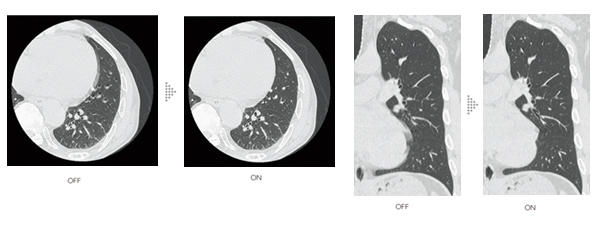

富士フイルムの経験とAI技術の活用により,被ばく低減と視認性を両立

IPV*3はAI技術を活用して開発した画像再構成技術です。充分な反復処理により得られる画像を教師データとして,高精度の処理を高速化しました。

AI技術を活用して設計された画像再構成IPV(最大 83% 被ばく低減)